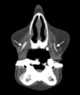

Nasolabial cyst

This nasolabial cyst, also known as a nasoalveolar cyst, is located superficially in the soft tissues of the upper lip. Unlike most of the other developmental cysts, the nasolabial cyst is an example of an extraosseous cyst, one that occurs outside of bone. [Source: Wikipedia ]